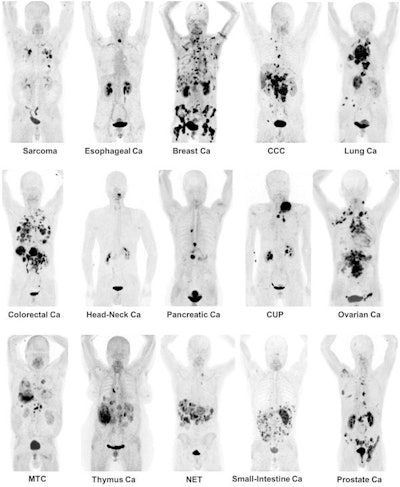

Maximum-intensity projection images of Ga-68 FAPI PET/CT in patients with 15 different histologically proven tumor entities (sorted by uptake in descending order). Ca = cancer; CCC = cholangiocellular carcinoma; CUP = carcinoma of unknown primary; MTC = medullary thyroid cancer; NET = neuroendocrine tumor. Images courtesy of Kratochwil et al and JNM."The remarkably high uptake of Ga-68 FAPI makes it useful for many cancer types, especially in cases where traditional F-18 FDG PET/CT faces limitations," added co-author Dr. Uwe Haberkorn, from the University Hospital of Heidelberg and the German Cancer Research Center, in a statement. "For example, low-grade sarcomas generally have a low uptake of F-18 FDG PET/CT, causing an overlap between benign and malignant lesions."

The researchers observed the highest average SUVmax (greater than 12) in cases of sarcoma, esophageal, breast, cholangiocarcinoma, and lung cancer. The lowest Ga-68 FAPI uptake (average SUVmax of less than 6) was seen in pheochromocytoma, renal cell, differentiated thyroid, adenoid cystic and gastric cancers. The average SUVmax of hepatocellular, colorectal, head-neck, ovarian, pancreatic, and prostate cancer was intermediate (SUVmax range, 6-12).